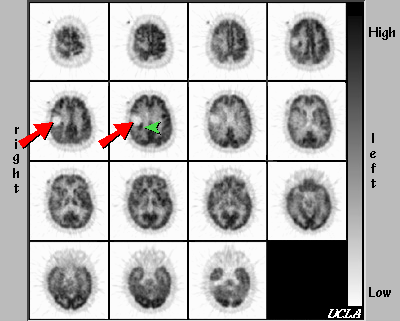

The region of ametabolism in right parietal lobe (red arrow) is consistent with resection. An area of hypermetabolism is seen in the posteromedial aspect of the surgical defect, suggesting tumor recurrence (green arrowhead). Other findings include a relative hypometabolism of the right posteroparietal cortex, and right thalamus, most likely due to radiation effects.Follow-Up

Rt. parietal craniotomy with gross total resection of brain tumor on 7/17/89. Recurrent glioblastoma confirmed on pathological examination